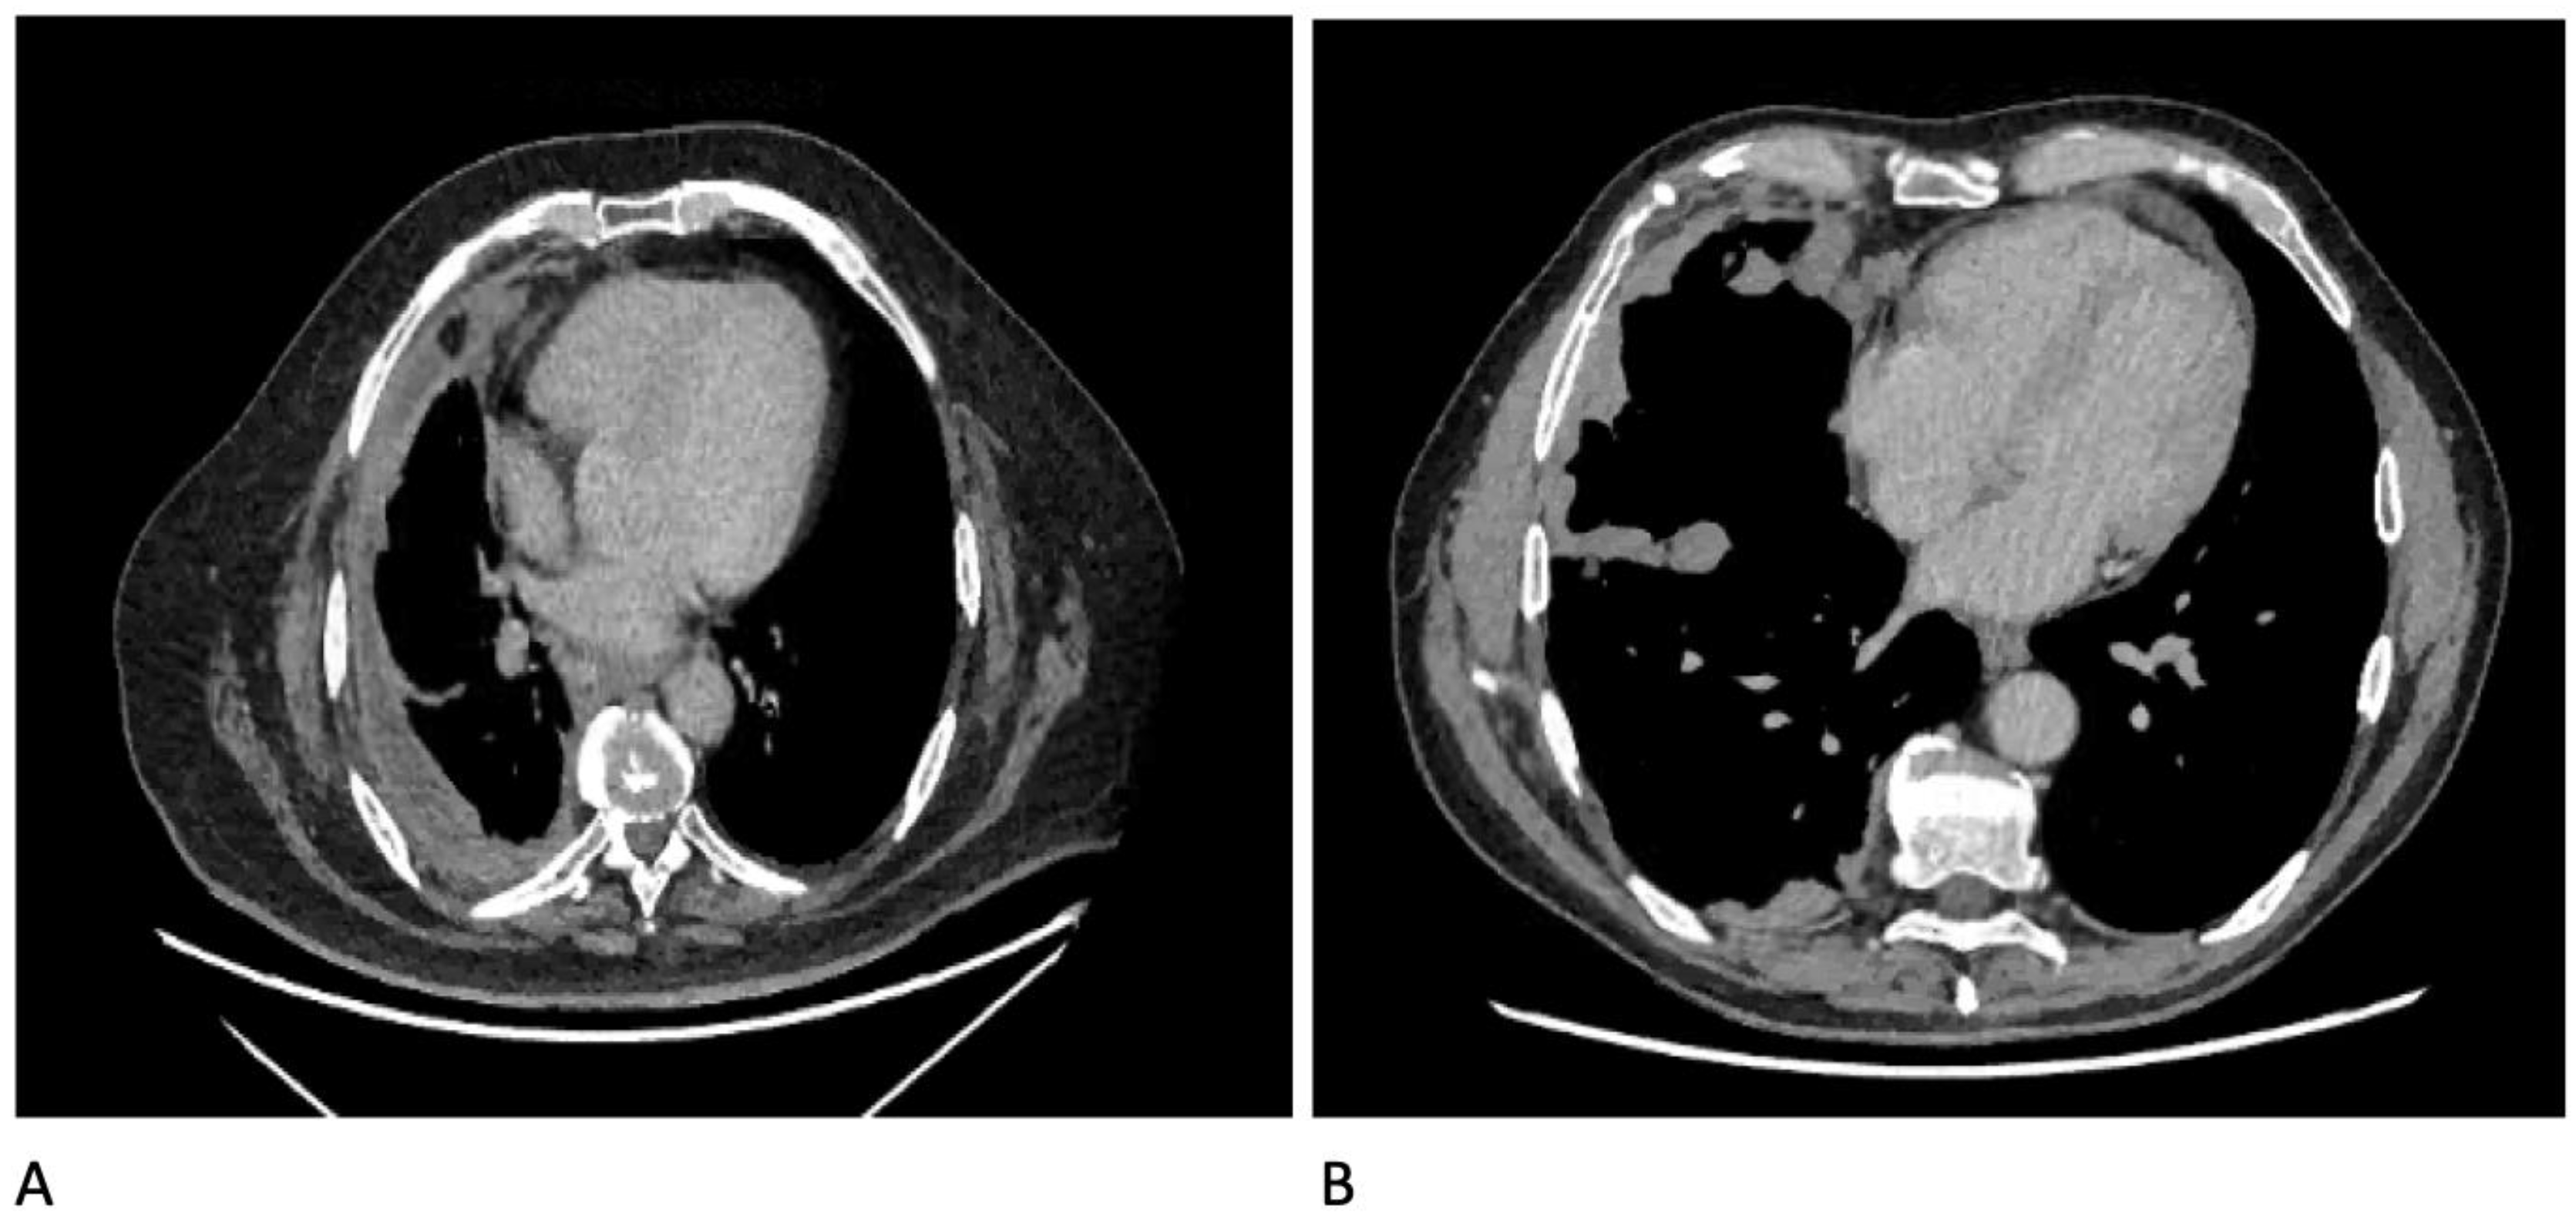

Diagnostics Free Full Text Diagnostics In Pleural Disease Html

Diagnostics Free Full Text Diagnostics In Pleural Disease Html

Diagnostics Free Full Text Diagnostics In Pleural Disease Html